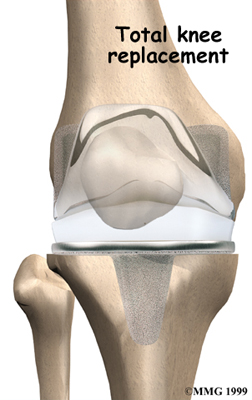

Artificial Knee Replacement

An artificial knee replacement is the ultimate solution for advanced knee OA.

Surgeons prefer not to put a new knee joint in patients younger than 60. This is because younger patients are generally more active and might put too much stress on the joint, causing it to loosen or even crack. A revision surgery to replace a damaged prosthesis is harder to do, has more possible complications, and is usually less successful than a first-time joint replacement surgery.

Related Document: FYZICAL West Sugar Land's Guide to Artificial Joint Replacement of the Knee